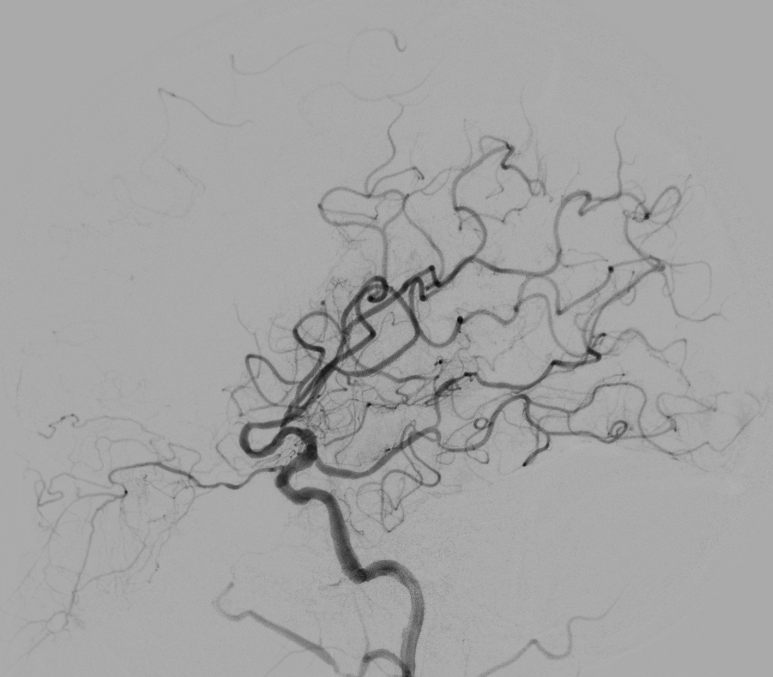

神经介入诊疗中心主任、副主任医师刘俊中接诊后,根据各项检查检验结果迅速判断张女士属于颅内大血管病变。

左侧大脑中动脉和颈内动脉均已闭塞,相当于左侧大脑半球几乎断了供血,手术指征明确。

5 分钟后,张女士被推进介入手术室,急诊脑血管造影进一步确认了血管闭塞情况。

10 分钟后,手术顺利完成,堵塞血管成功开通,濒临坏死的脑细胞被及时 “救回”,张女士的病情得到了有效控制。